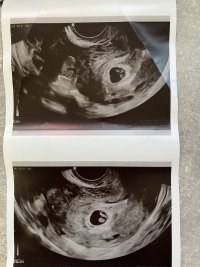

Etter 2 MA er det en ubesrkivelig følelse å få se hjertet. Krysser alt for at det fortsetter sånn. Ble satt frem to dager til 9+0